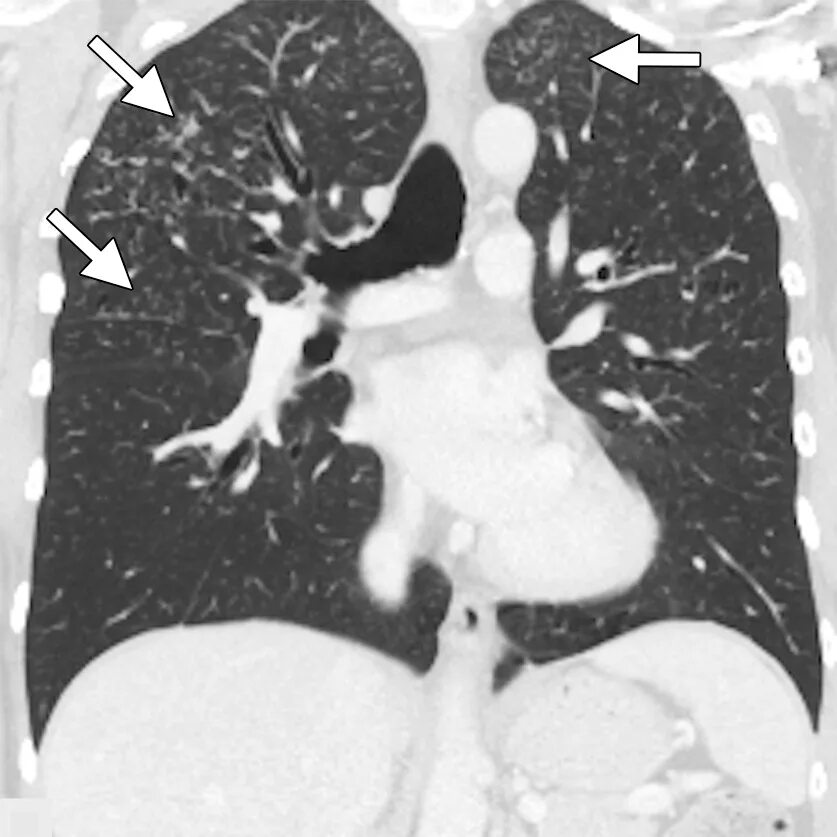

Кт х